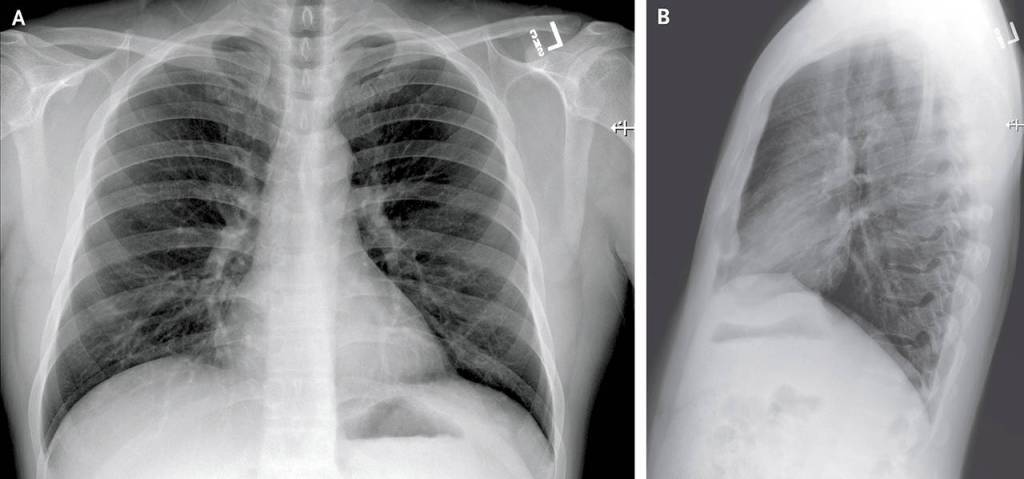

Posteroanterior and Lateral Chest Radiographs, January 19, 2020 (Illness Day 4).No thoracic abnormalities were noted (Snohomish Health District)